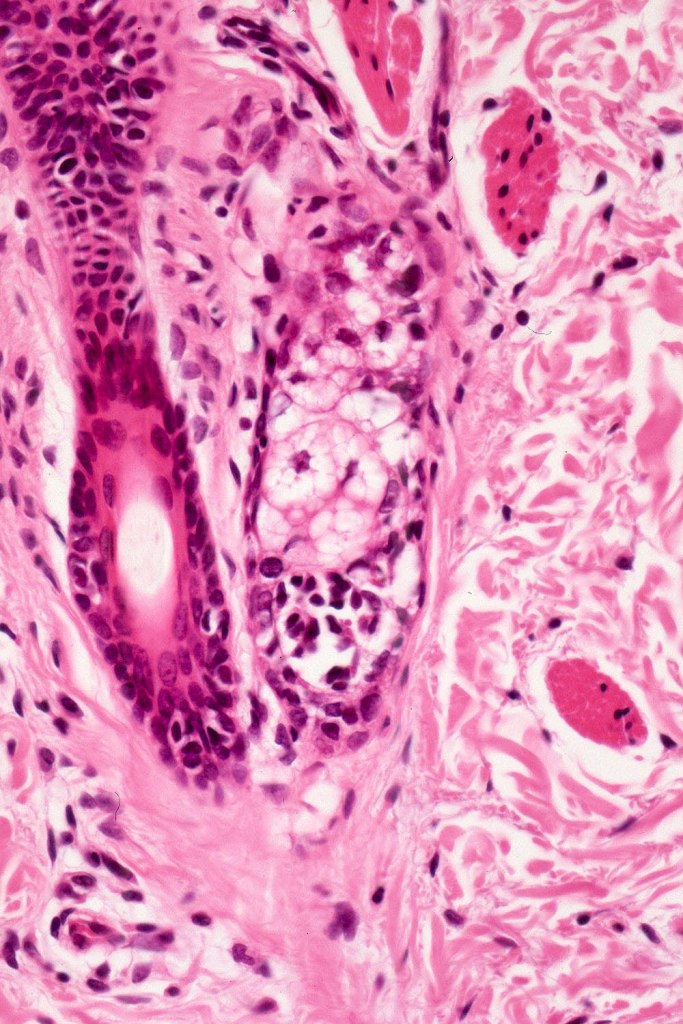

•Perineural sheath infiltration

•Blood vessel and lymphatic wall infiltration

This melanoma arose in a small congenital nevus of the scalp. It metastasized widely. Varying features in different fields.